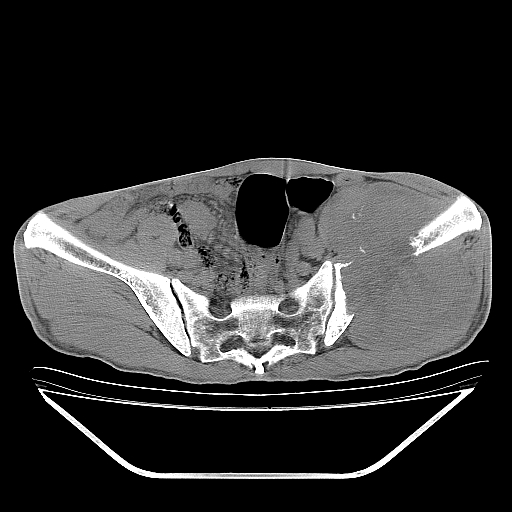

以下是引用天南地北在2007-10-4 18:01:00的发言:[br][br]考虑左髂部恶性肿瘤(溶骨性骨质破坏+软组织肿块影+残留骨质);以滑膜肉瘤可能性大。[br]建议穿刺活检

以下是引用liuyue在2007-10-4 23:38:00的发言:[br]左髂部恶性肿瘤,建议穿刺活检,或先做肺部检查,除外肺癌转移之可能。